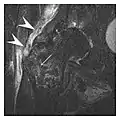

The greater tuberosity of the humerus is also an illustrative location of occult fractures. The osseous injury may follow seizures, glenohumeral dislocation, forced abduction, or direct impaction. They are commonly discovered on MRI in symptomatic patients with suspicion of rotator cuff tear. Coronal images are best suited for detection. They appear as crescentic oblique lines surrounded by a bone marrow edema pattern (Figure 5). The rotator cuff must be inspected since associated ligamentous lesions are common. In the ankle, malleoli and tarsal bones should be checked carefully for any cortical disruptions and radiolucent lines that may reveal a fracture. Awareness of the exact location of the pain will help direct the attention of the interpreter when searching for very subtle signs of fracture (Figure 6).[1]

Figure 5: Traumatic fracture of the greater tuberosity in a 51-year-old man presenting with left shoulder pain after a fall on ice. Initial radiographs were normal. Coronal inversion recovery MRI shows a fracture line (arrow) through the greater tuberosity surrounded by a bone marrow edema pattern.[1]